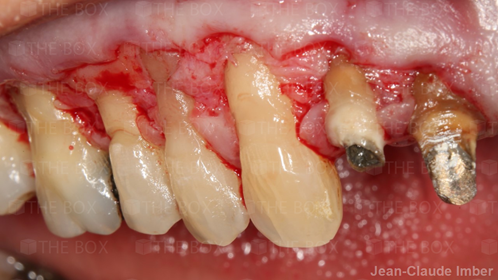

A new case was made public by Jean-Claude Imber check it out here.